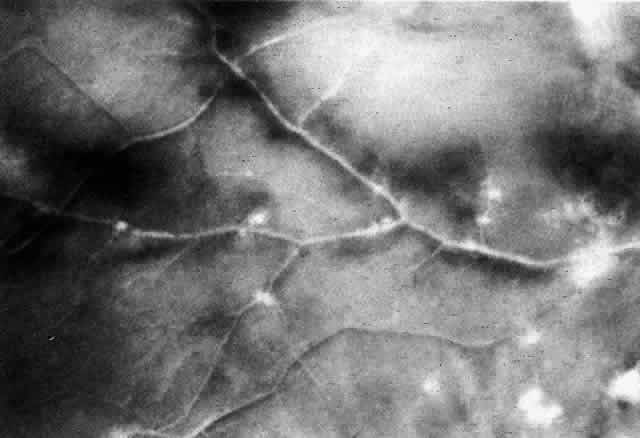

The histopathologic characteristics of AIDS-related CMV retinopathy in one autopsy study are listed in Table 3.9 CMV retinopathy frequently begins adjacent to retinal vessels in the posterior pole (Fig. 2). It is believed that virus reaches the eye via the bloodstream. Untreated CMV retinopathy in patients with AIDS is a relentlessly progressive disease. Usually, infection begins with an isolated focus of disease; rarely are there more than two or three discrete areas of infection within the eye. These lesions invariably enlarge to involve additional retinal tissue. New lesions develop less frequently. The enlargement of lesions does not progress at the same rate from all lesion borders.21 The rate of progression is faster in an anterior direction toward the ora serrata than in a posterior direction toward the fovea. CMV retinopathy has been considered a “foveal-sparing” disease. In a series of organ transplant patients with CMV retinopathy reported by Egbert and associates prior to the AIDS epidemic, only 3 of 21 eyes had macular involvement.14 The higher incidence of macular involvement in early autopsy series of patients with AIDS may reflect the fact that progression of CMV retinopathy into the macular region could not be stopped prior to the introduction of ganciclovir and foscarnet therapy. Even though the fovea can eventually be destroyed, it is usually the last area to become infected; in some cases the disease appears to move circumferentially around the fovea (Fig. 3). Eventually the entire retina will be destroyed, usually within a 6-month period.19 Progression of the retinopathy halts abruptly at the ora serrata.9 Following total retinal necrosis, it is replaced by a thin gliotic membrane.19 No virus can be identified in ocular tissue at this late stage.